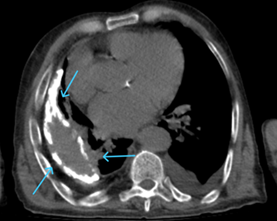

The duration of his anti-tuberculosis treatment and the specific medications he got remain unknown. He has a smoking history of 20 packs per year, has been smoke-free for 35 years, and abstains from alcohol consumption. He had hypertension and heart failure, but the patient had no history of regular drug use. He has been having frequent coughs, phlegm and shortness of breath for about 20 years. He was given oral antibiotic treatments, but when his complaints started to regress, he did not go for follow-up examinations. He used oral antibiotics 4 times in the last year, and hospitalization was recommended once, but the patient did not accept it. Looking at the patient's retrospective examinations, pleural thickening, areas containing fluid density, and calcifications were observed in the right hemithorax in the Thorax CT scans taken in 2010 and 2022 (Figures 1 & 2). In the CT scan of the patient taken in January 2024, approximately 3,5 cm was observed on the right hemithorax, which could be evaluated in favor of pleurisy sequelae (Figures 3 & 4). Sputum analysis for three Acid-resistant bacilli tests was negative. There is no elevated sedimentation, CRP, or leukocytosis.

Figure 4 Paranchimal window of January 2024 thorax CT, the calcific structure of the lesion is not observed in this window, and if it was not evaluated with old imaging and the mediastinal window, it could be evaluated as acute empyema/parapneumonic effusion.

In chronic calcified pleurisy, which is evaluated in favor of sequelae in patients with appropriate history and clinical findings, the etiology should be elucidated, and treatment options should be assessed without causing the patient's clinic to deteriorate. Assessing patients without seeing previous radiological images can result in inaccurate diagnostic procedures and result in time wastage in patient care.

A calcific empyema that has been stable for years should be carefully considered in terms of potential consequences, such as bronchopleural fistula. The article highlights that chronic calcific empyema, a condition that is infrequently encountered in clinical settings, can frequently be mistaken for acute empyema and parapneumonic effusion with circumstances where prompt diagnostic choices are required, such as emergency rooms and critical care units. It is important to compare radiological findings with any previous imaging, if available, and make decisions on an individual basis for the accurate diagnosis and treatment approach.